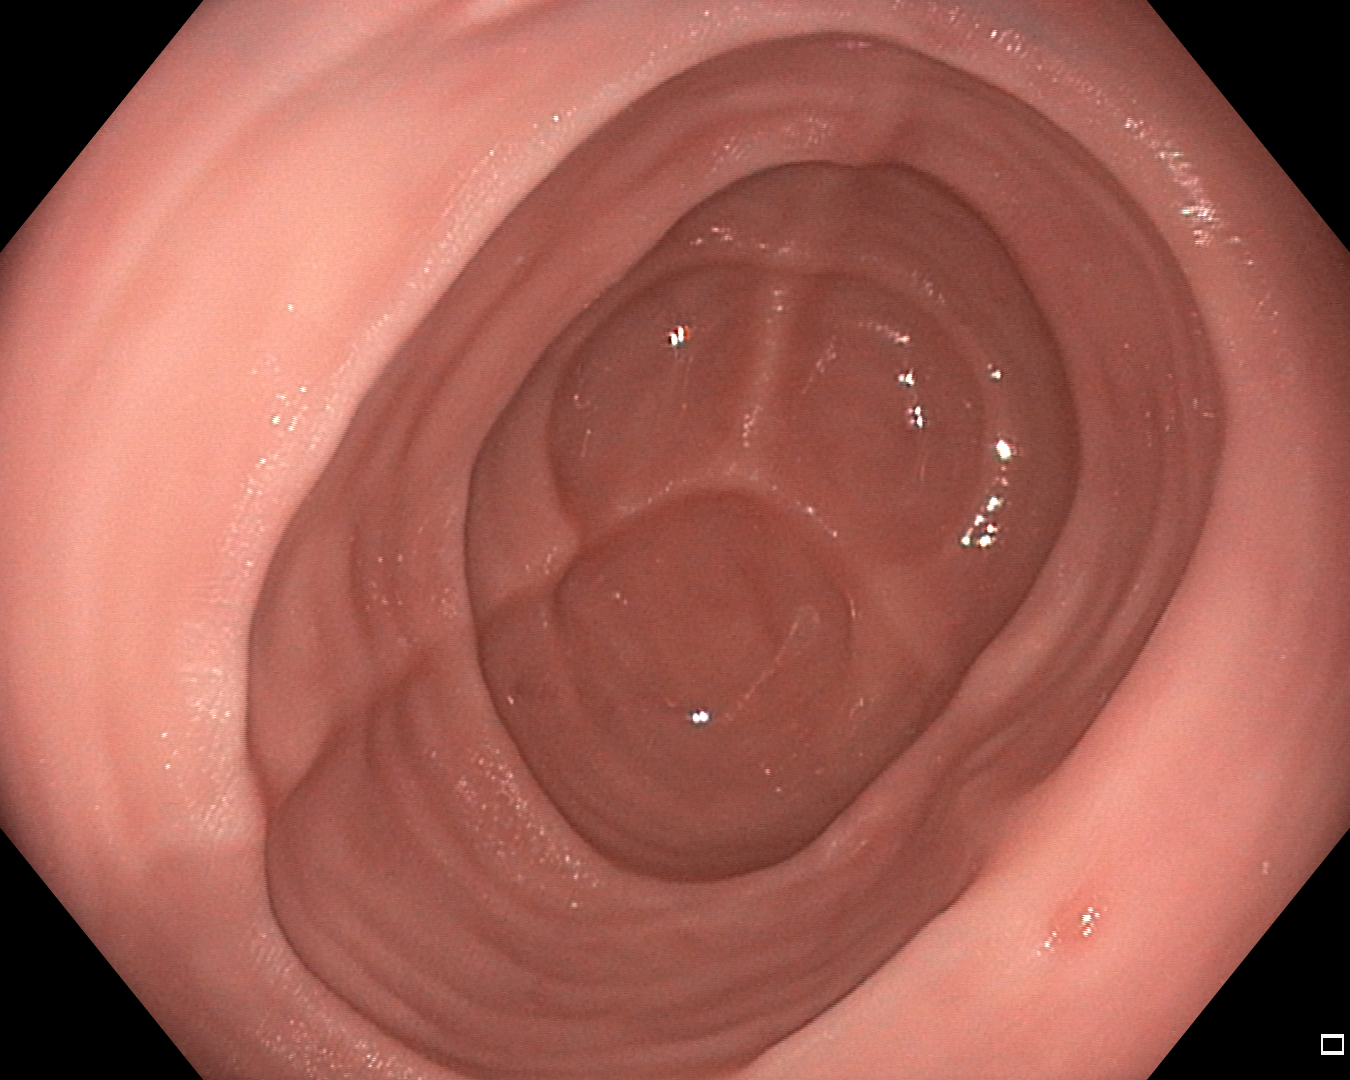

VI Semantic segmentation

Semantic segmentation is the problem of determining which, out of a predefined set of classes, each pixel in an image should be assigned to. In the context of GIE, the predefined set of classes will typically include a background class that accounts for anything that is not of interest, as well as any classes that are of interest, for example, polyps, tools, artefacts, or disease. In this section, we detail and present our evaluation of the fine-tuned performance of backbones in polyp segmentation specifically, which is notably a binary segmentation problem.

For all metrics, a higher value indicates better performance. The results for Kvasir-SEG are presented in Table VII and the results for CVC-ClinicDB are presented in Table VIII. Examples for Kvasir-SEG are shown in Fig. 2.